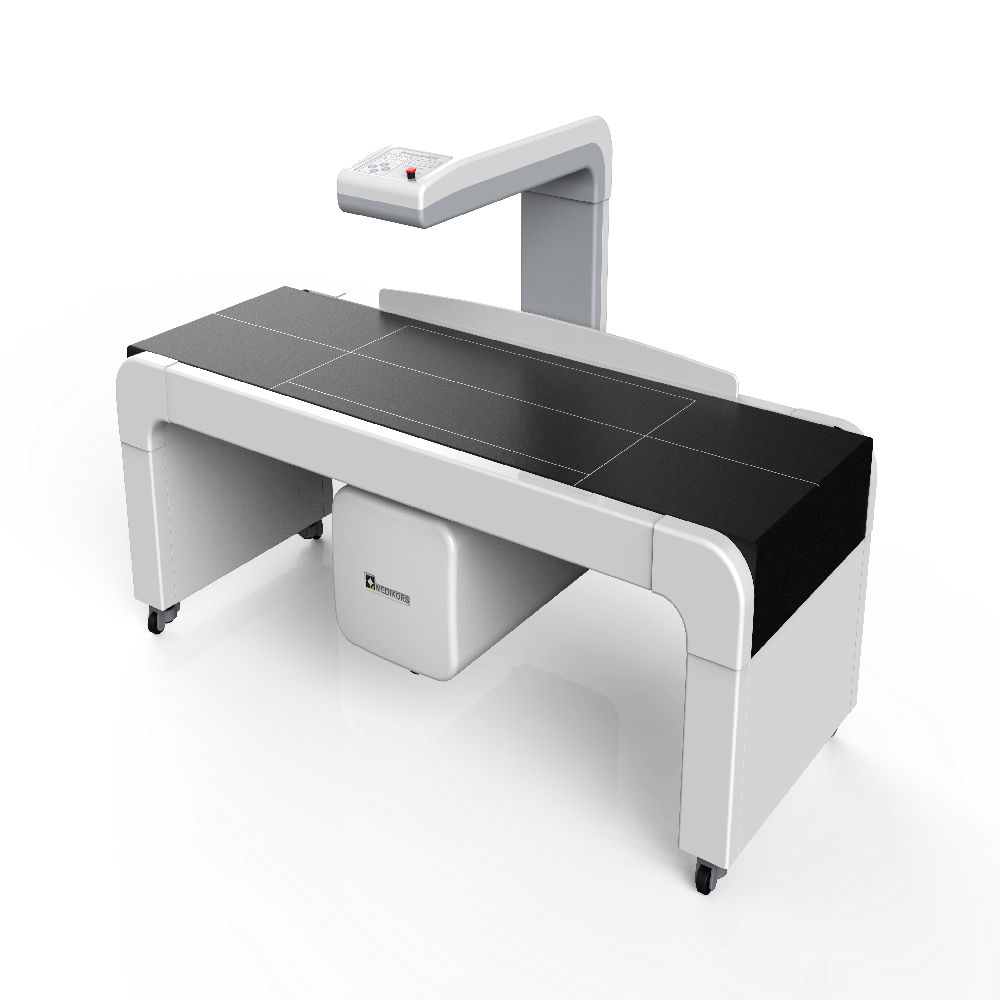

Model InAlyzer AIRMEDIKORS

1850*800*1162 mm/ 138 kg

64 channel DXA Bone Densitometry

InAlyzer AIR uses 64 ch dual energy x-ray detector based on Fan Beam technology and obtains 64 rows of data per one x-ray irradiation, enabling acquisition of data of higher resolution in a shorter time, unlike pencil beam system that obtains 1 row of data per one x ray irradiation. Also the reliability and durability was enhanced by using an x ray generator that does not require fast switching between high energy and low energy, and the x ray detector that acquires high resolution data of high energy and low energy independently provides high-quality images.

InAlyzer AIR has an open design for the first time in the world, and this results in not only a chic design but also, by locating the moving axis to the center of the moving part, minimizing the shaking between the X ray generation and x ray detection section during the scan and, thereby, maintaining accuracy in the measurement result.

1. High resolution and fast measurement

By applying the energy-fixed x-ray generator, we minimized the failure rate, while the energy-independent high-resolution detector provides fast high resolution results.

2. Wide inside & Compact outside

Our own equipment technology maximized the scan are, minimizing the patient's movement and external size for space efficiency in hospitals.

4. Excellent & Robust design

As a product of a national R&D project, the equipment features a chic design, including the world-first open of its kind, reduced rate of errors caused by vibration during scanning, and therefore, high levels of accuracy and precision.